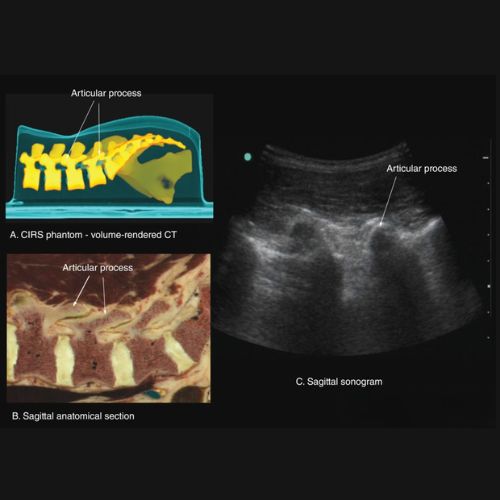

Sonography

Used for evaluating soft tissue, muscle, and nerve health in select spine and joint conditions.